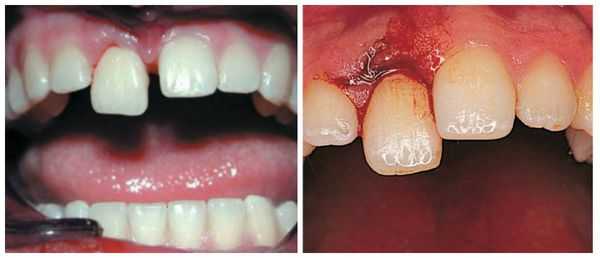

- Полный вывих: сопровождается сильной болью; зуб в лунке отсутствует; пустая лунка кровоточит; десна изменена в цвете; имеется припухлость; может возникнуть гематома; происходит локальное повышение температуры; некоторое время могут наблюдаться дефекты речи.

Полный вывих характеризуется полным разрывом волокнистых структур периодонта (в том числе круговой связки зуба). При этом травмированный зуб в лунке отсутствует, а сосудисто-нервный пучок зуба всегда разрывается. Вывих может сопровождаться переломом края альвеолы. Иногда зуб может присутствовать в альвеоле за счёт единичных сохранившихся волокон круговой связки. По статистике полному вывиху чаще подвергаются фронтальные зубы верхней челюсти, реже — нижней. Меньше других подвержены полному вывиху клыки.

Лечение полного вывиха

В случае полного вывиха зуба, если с момента травмы прошло не более двух суток, проводится его реплантация (установка зуба обратно в лунку) [8] .

Чем раньше проводится реплантация, тем выше вероятность положительного результата. Резорбция корня в данной ситуации менее выражена и протекает медленнее.